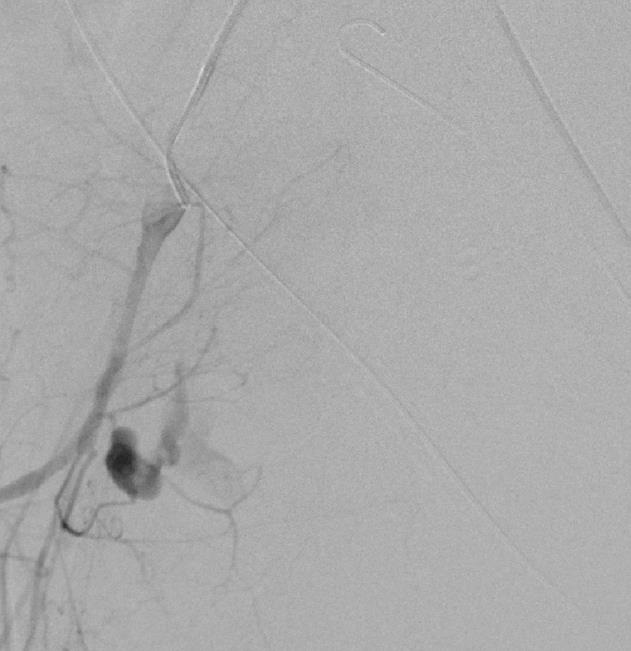

肺动静脉畸形

肺动静脉畸形分为单发、多发和弥漫性 |

这一例为多发性肺动静脉畸形 |

显示巨大静脉池显影 |

回流至肺静脉 |

肺动静脉畸形

选择其中一支畸形的滋养动脉 |

造影剂经静脉池回流至肺静脉 |

造影剂经静脉池回流至肺静脉 |